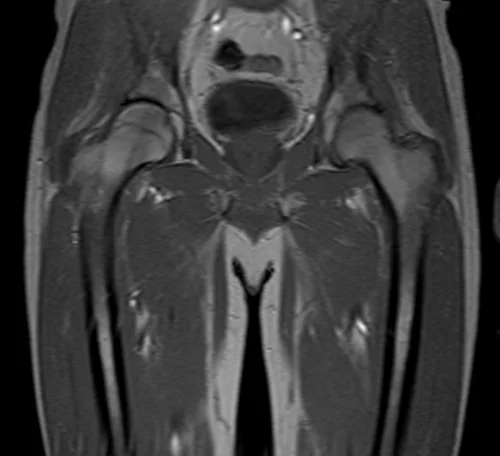

mri hipa localizer 2 - MRI